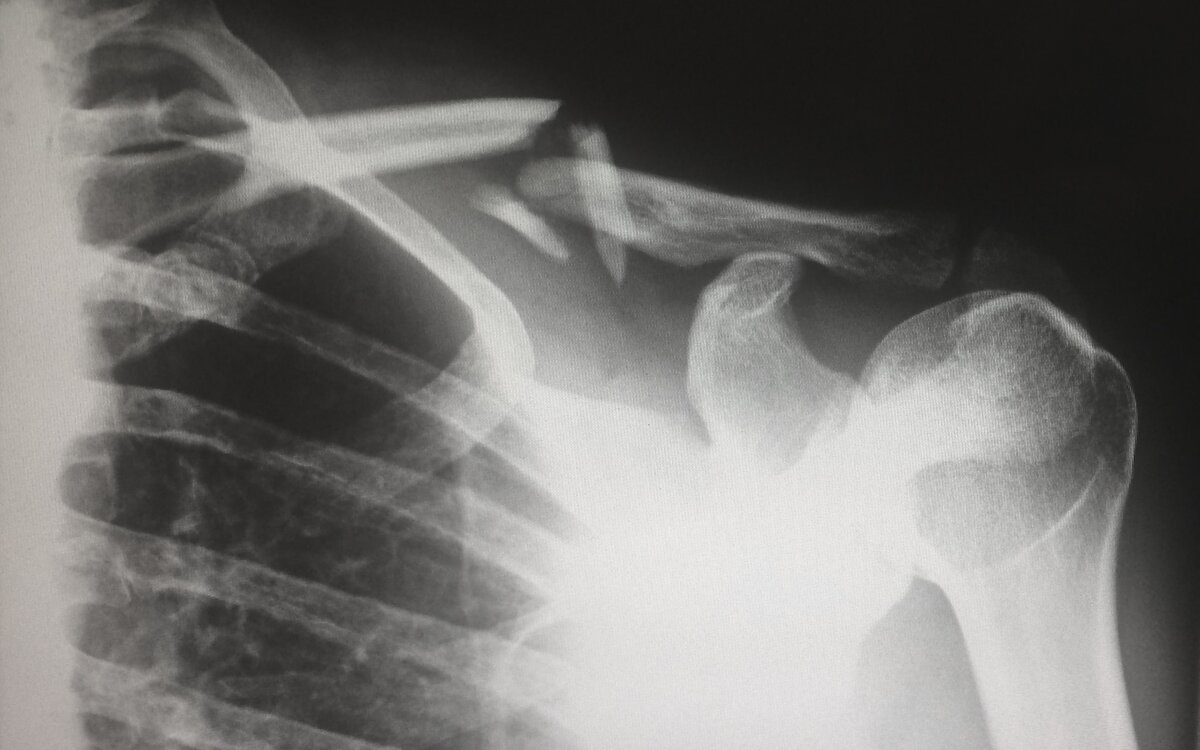

Атипичные переломы бедер – это низкоэнергетические переломы, которые возникают из-за ослабления внешнего края бедренной кости. Клиническая картина обычно включает боль в области бедра или паха, которая возникает после поднятия тяжестей. С целью профилактики этих переломов рекомендуется временно прекратить лечение бисфосфонатом после 5-летнего приема пероральных форм или после 3-летнего введения венозного препарата.